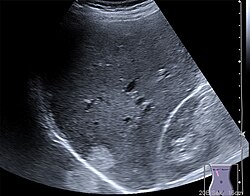

Die Sonografie ist das wichtigste Verfahren bei der Differentialdiagnose eines akuten Abdomens, bei Gallensteinen oder bei der Beurteilung von Gefäßen und deren Durchlässigkeit, vor allem an den Beinen. Weiterhin wird sie standardmäßig zur Untersuchung der Schilddrüse, des Herzens – dann Echokardiografie oder Ultraschallkardiografie (UKG) genannt –, der Nieren, der Harnwege und der Harnblase benutzt. Durch den Einsatz von Echokontrastverstärkern (Kontrastmittel) ist in geeigneten Fällen eine weitere Verbesserung der Diagnostik möglich.

Alle wasserhaltigen, blutreichen Organe sind für den Ultraschall gut untersuchbar. Schlecht untersuchbar sind alle gashaltigen oder von Knochen bedeckten Organe, zum Beispiel der Darm bei Blähungen, die Lunge, Gehirn und das Knochenmark. Manche Organe sind im Normalzustand nur schwierig, im krankhaft vergrößerten Zustand dagegen gut erkennbar (Blinddarm, Harnleiter, Nebennieren).

Das Verfahren hat in tief gelegenen Geweben eine geringere Raumauflösung als die CT und MRT. Auch die Weichteil- Kontrastauflösung kann der bei der MRT unterlegen sein. Gas und Knochen verhindern die Ausbreitung der Ultraschallwellen. Daher ist die Sonografie bei gasgefüllten Organen (Lunge, Darm) und unter Knochen (Schädel, Rückenmark) erschwert. Anders als bei anderen bildgebenden Verfahren gibt es keine standardisierte Ausbildung. Daher bestehen große qualitative Unterschiede in den diagnostischen Fähigkeiten der Anwender.